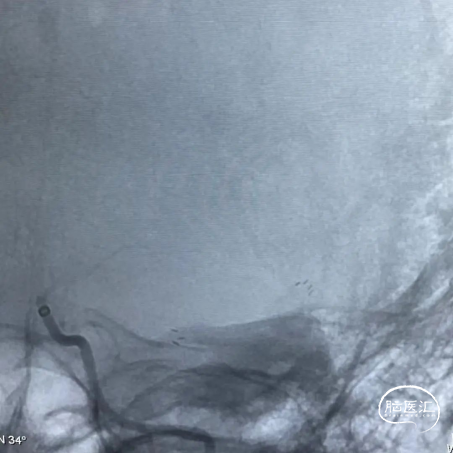

手术过程

患者全麻成功后,取平卧位于造影床上,选取右侧股动脉为穿刺点,按Seldinger法穿刺右侧股动脉,成功后置入8F动脉鞘。

长鞘在125cm造影管和0.035inch导丝辅助下,将长鞘带至左侧颈总动脉分岔处,将6F 125cm颅内支撑导管在0.035inch导丝辅助下超选至左侧颈内动脉岩骨段。

造影示:左侧大脑中动脉M2段管腔纤细、重度狭窄,测量狭窄约80%左右,远端血流缓慢,未见动脉瘤及血管畸形,拟行左侧大脑中动脉M2狭窄段球囊扩张开通支架植入成型术。

使用0.014inch微导丝塑形后辅助微导管通过左侧大脑中动脉狭窄段到达M3远端,造影确认微导丝在血管真腔,交换神经微导丝超选至左侧大脑中动脉M3远端。将6F 125cm颅内支撑导管在交换导丝及微导管支撑辅助下超选至左侧颈内动脉交通段,撤出微导管,交换加奇生物Fastunnel®输送型球囊扩张导管至狭窄病变血管处。

使用压力泵充盈Fastunnel®输送型球囊扩张导管扩张病变血管两次。造影见左侧大脑中动脉狭窄基本扩开。

患者血管弹性差,拟支架置入术,撤出微导丝,通过21系列 Fastunnel®输送型球囊扩张导管释放自膨式闭环支架完全覆盖狭窄血管,退出Fastunnel®,再次造影见颅内血流较术前有所改善,脑循环时间好转。遂结束手术,拔出动脉鞘压迫15分钟后加压包扎。